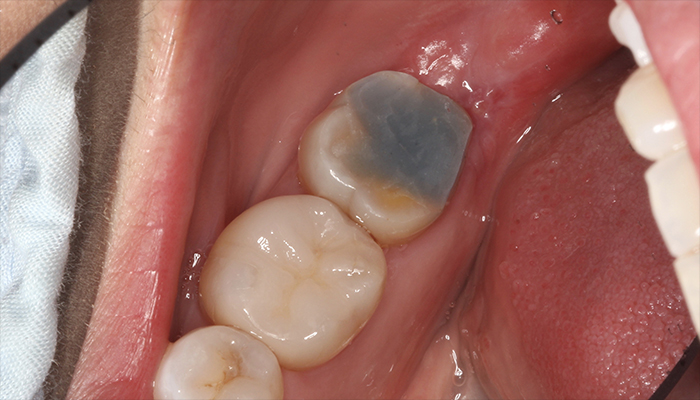

術前

術後

歯周ポケットの問題も改善され、清掃しやすい状態になっています。